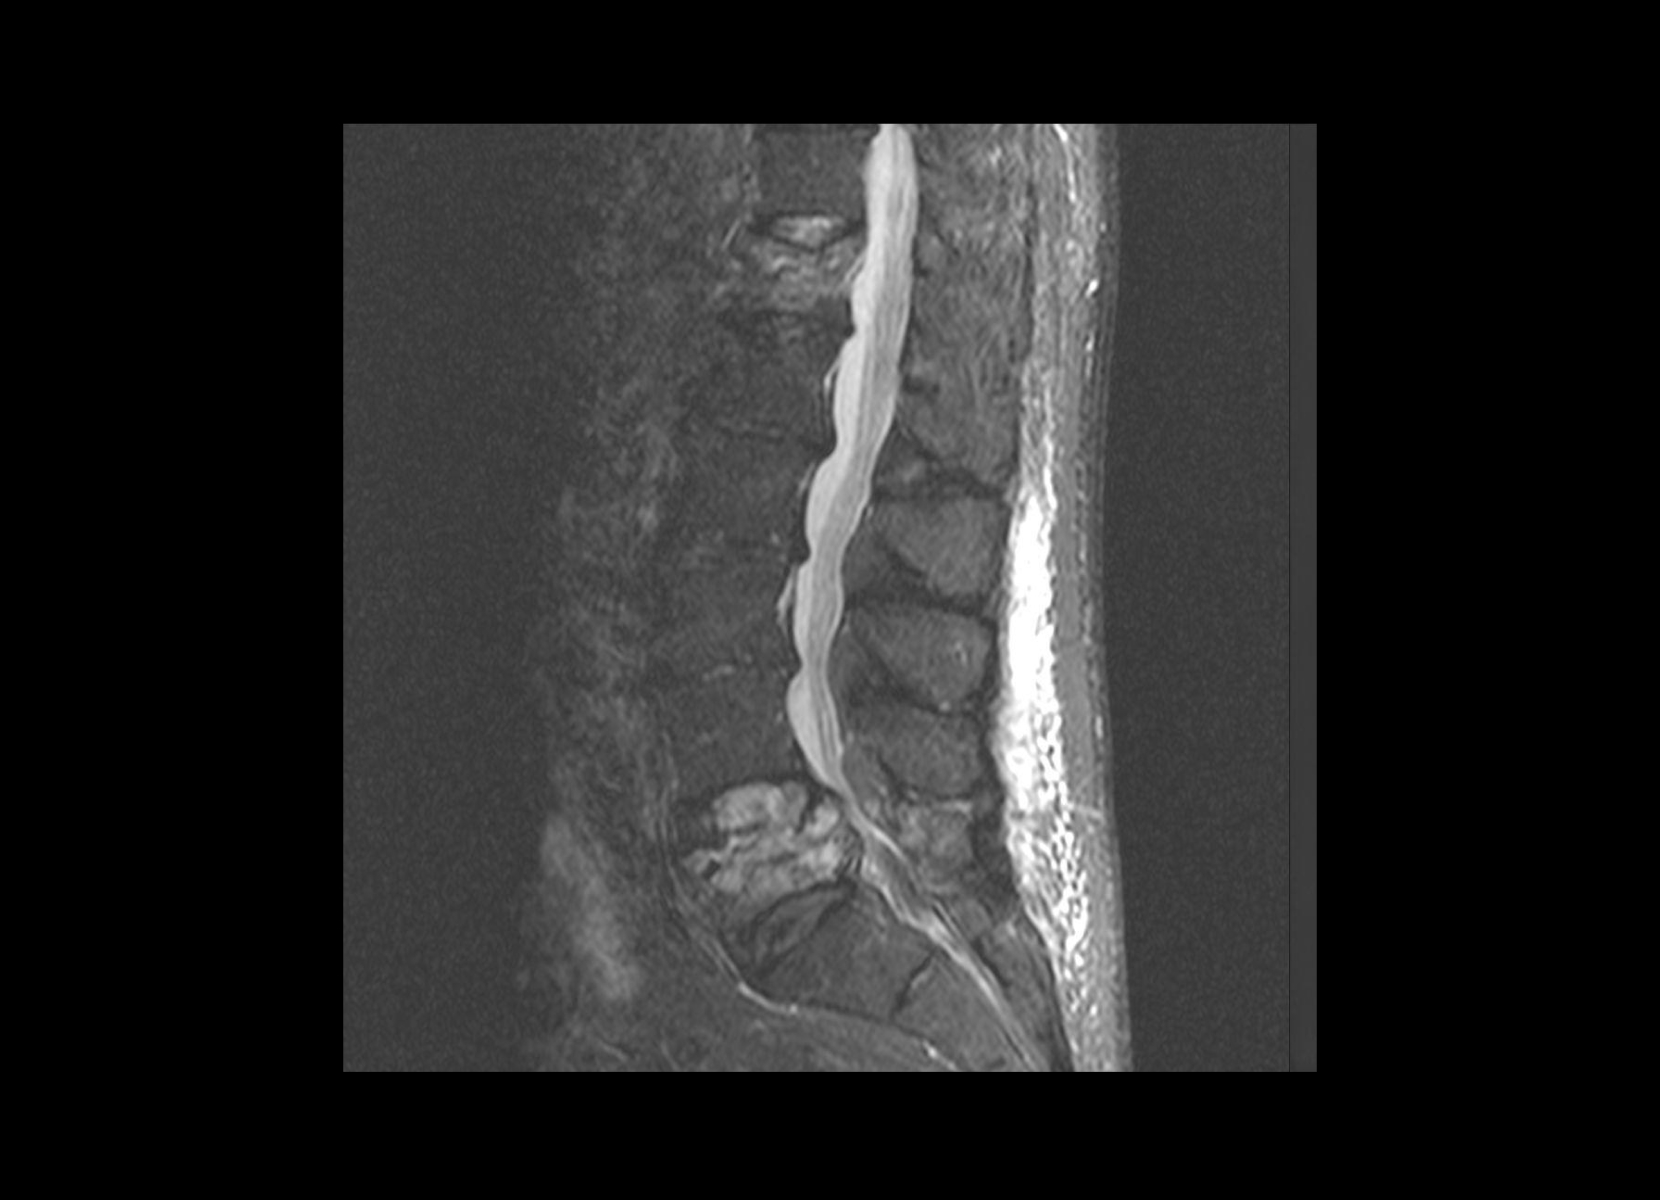

Trauma

GE 1.5T

C-spine

Conventional

STIR

SubtleSYNTH™

(Synthesized STIR)™